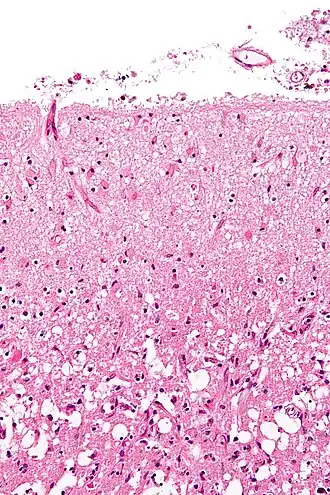

Histopathology at high magnification of a normal neuron, and an ischemic stroke at approximately 24 hours on H&E stain: The neurons become hypereosinophilic and there is an infiltrate of neutrophils. There is slight edema and loss of normal architecture in the surrounding neuropil.

Various microscopic findings are present at times from infarction as follows:[32]

An autopsy of stroke may be able to establish the time taken from the onset of cerebral infarction to the time of death.